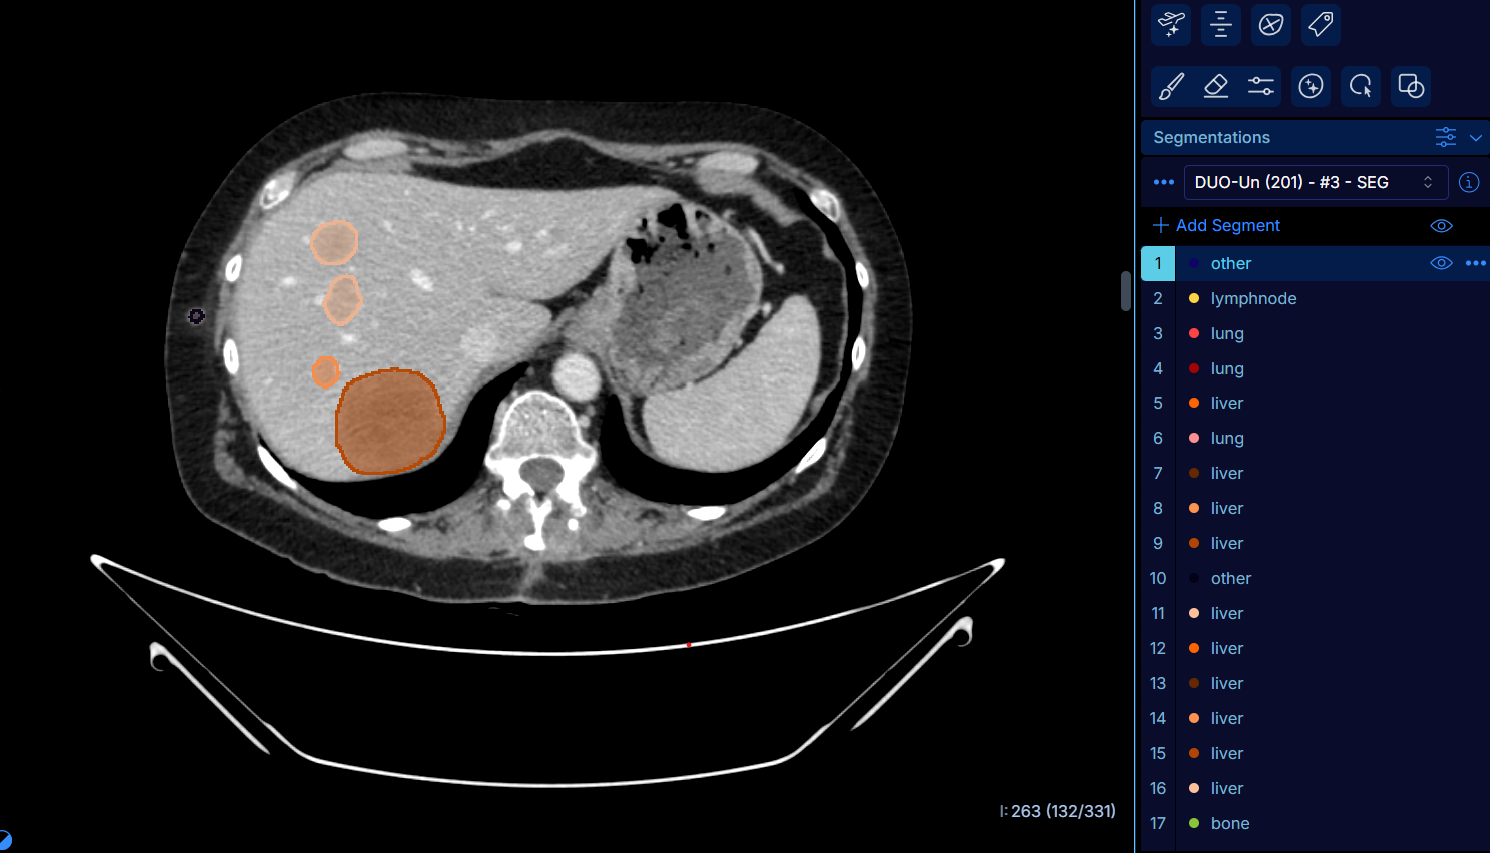

coupe_FAST_DuOnco_crédit Gustave Roussy

Cet outil, baptisé DuOnco Unity, repose sur un algorithme d’IA à même de détecter automatiquement et en trois dimensions l’ensemble des tumeurs et des métastases visibles sur un scanner thoraco-abdomino-pelvien. Cette analyse permet de mesurer la charge tumorale réelle des patients dans cette zone et de générer des indicateurs pour prédire l’évolution de la maladie.

DuOnco Unity, à la fois multi-organes et multi-anatomique, est un outil unique au monde. Il fonctionne sur l’ensemble du thorax, de l’abdomen et du pelvis, et est également capable d’analyser les ganglions lymphatiques, une fonctionnalité rare et particulièrement utile puisqu’ils représentent l’un des principaux sites métastatiques. Enfin, il intègre la masse musculaire et les tissus adipeux dans ses comptes rendus, des indicateurs importants pour établir un diagnostic précis en oncologie.